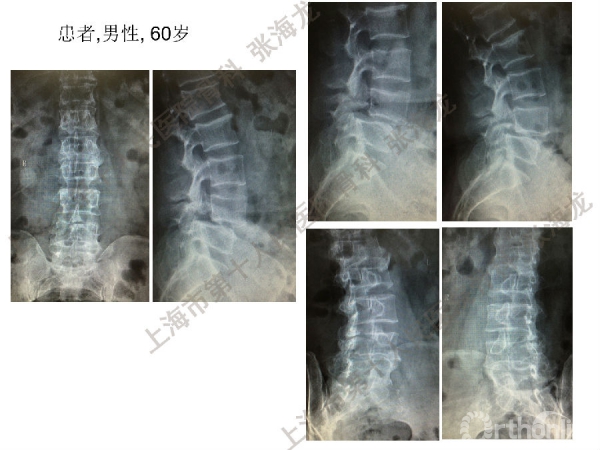

2008年3月至2010年8月,上海市第十人民医院骨科随访49例腰椎滑脱症(峡部裂型和退变型)患者,对比23例微创手术MIS-TLIF和26例开放手术治疗腰椎滑脱症的临床及影像学结果,进行了回顾性研究。

研究发现,Wiltse入路Mis-TLIF更直接的暴露峡部及关节突,对脊柱稳定性的影响较小;彻底松解辅助双重提拉复位Mis-TLIF,对于峡部裂型滑脱有较好的复位效果;对于峡部裂型滑脱,提拉复位在影像学参数上有一定优势;与原位融合相比,ODI.VAS.JOA无明显差异(样本量有限);对于退变性滑脱,单纯撑开椎间隙与原位融合可以获得较好疗效。